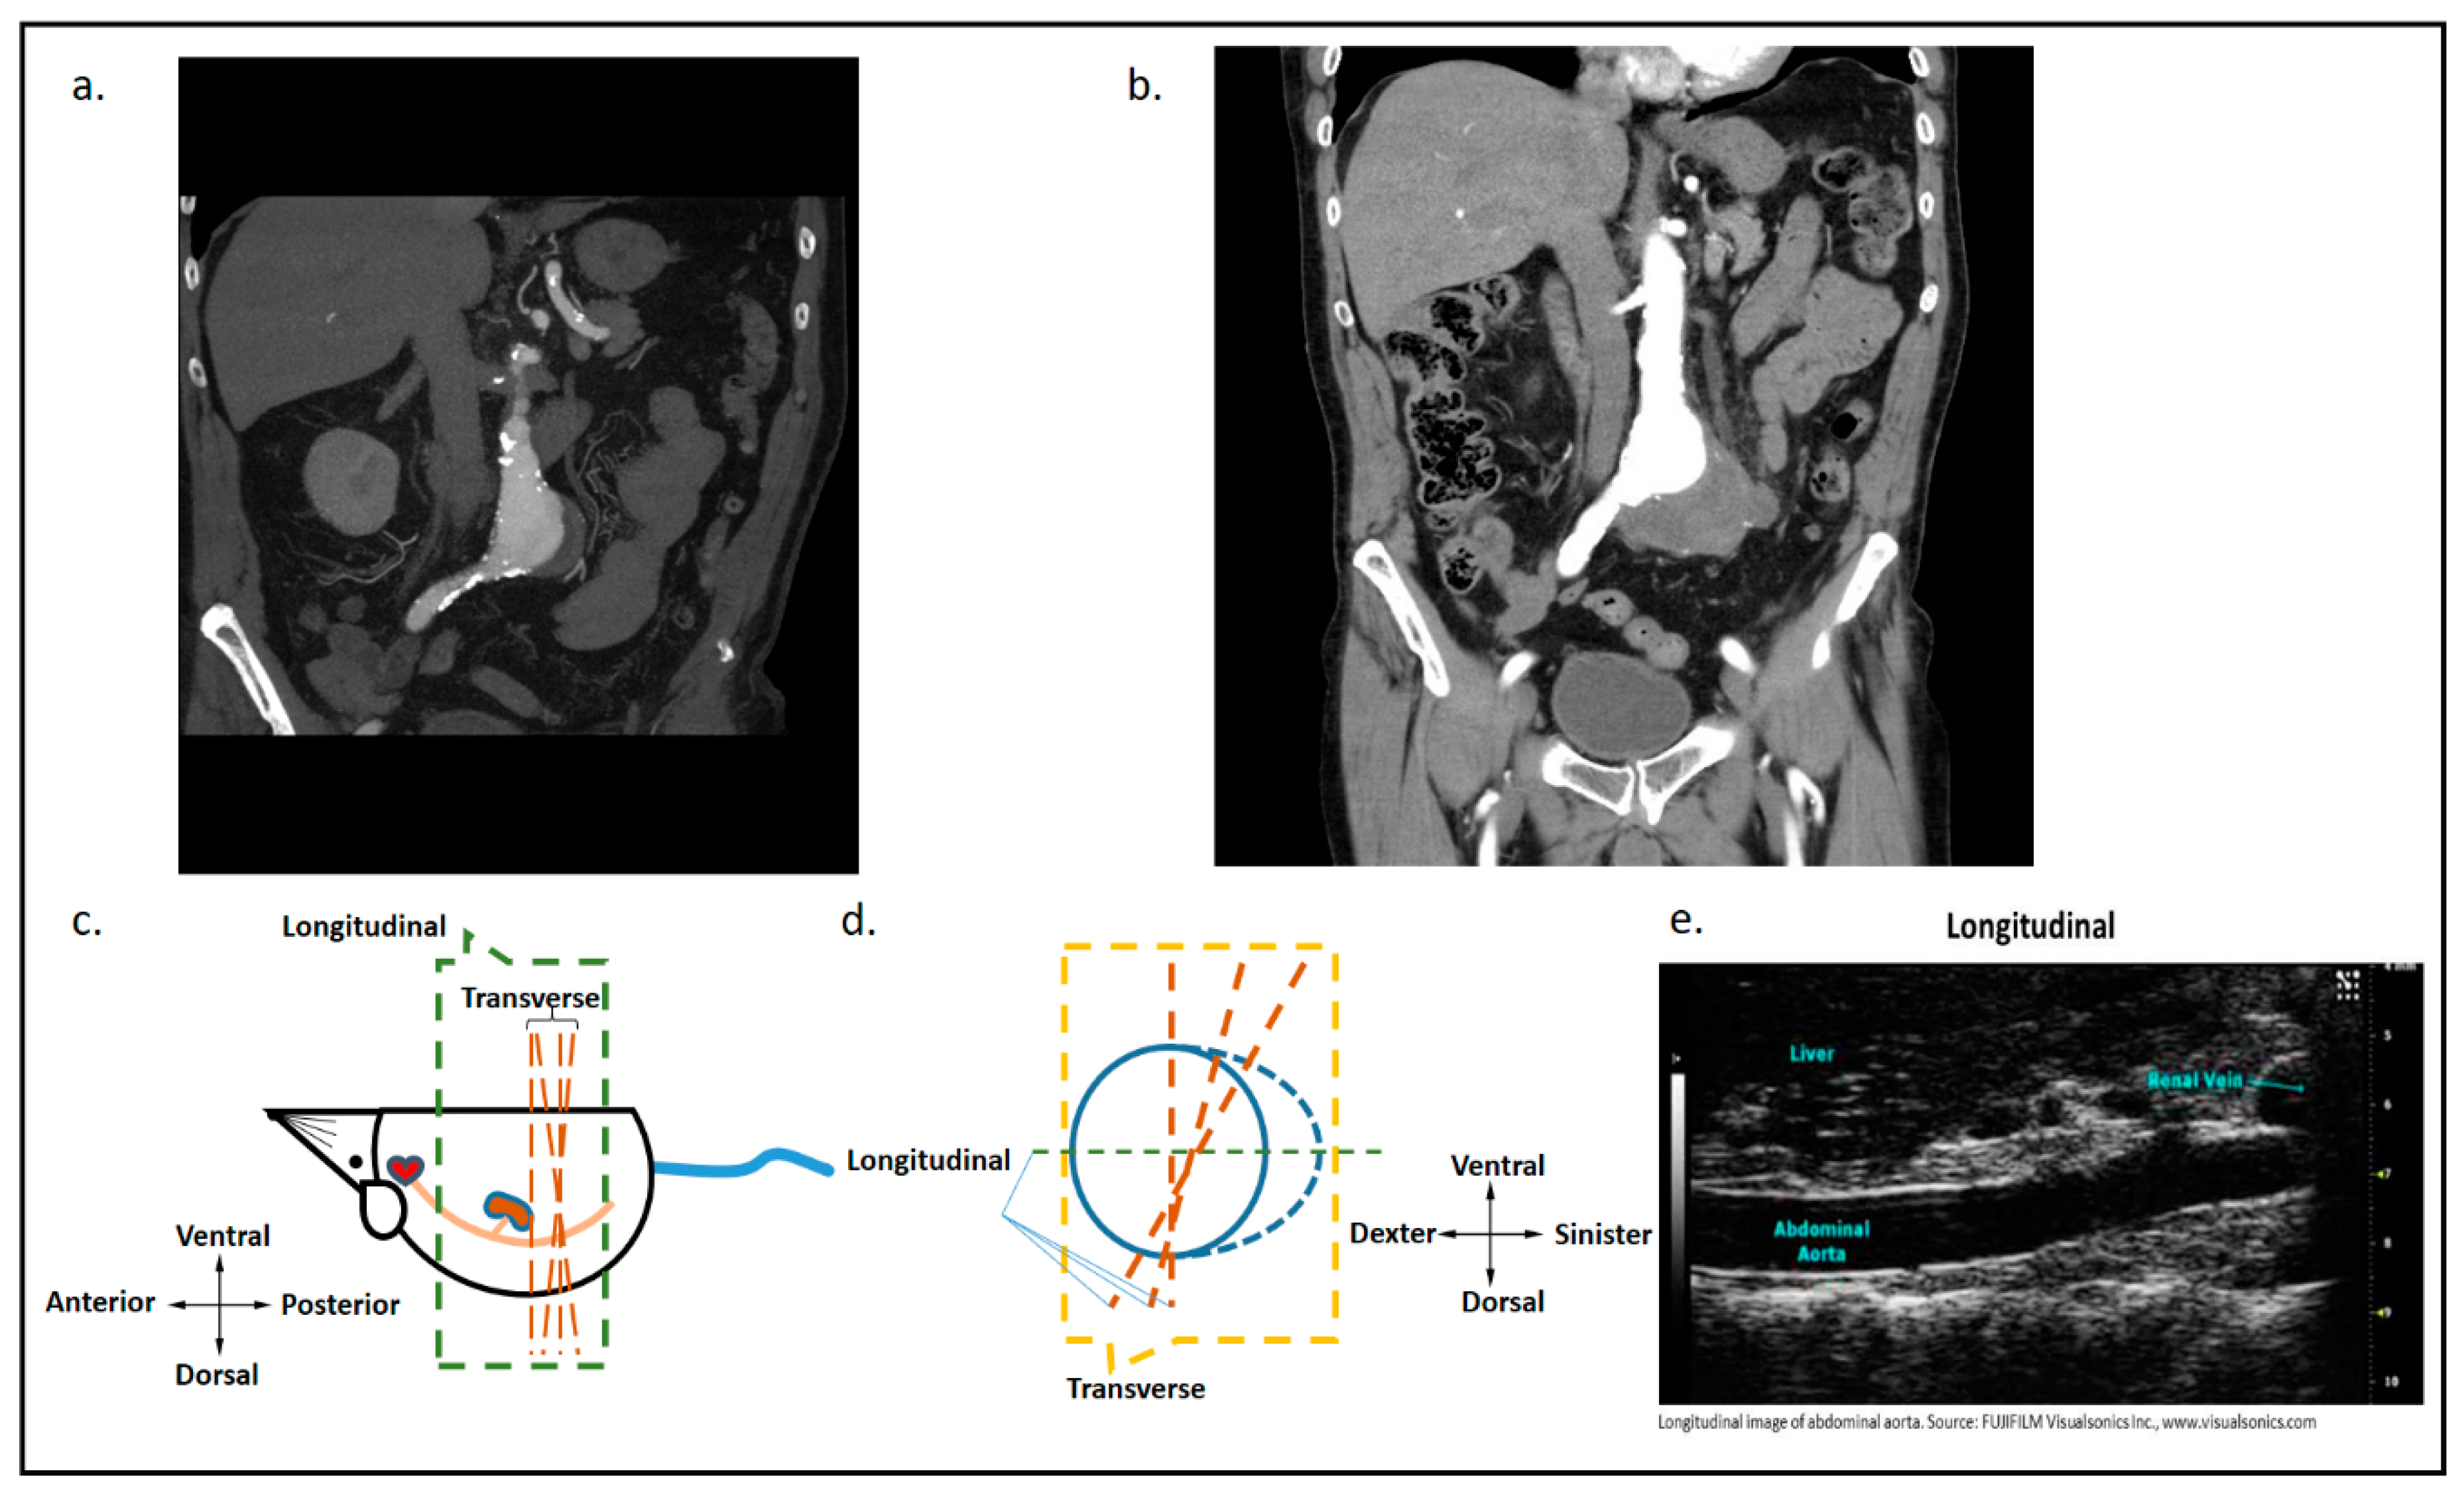

5.1. High-Resolution Ultrasound to Study AAA Rupture